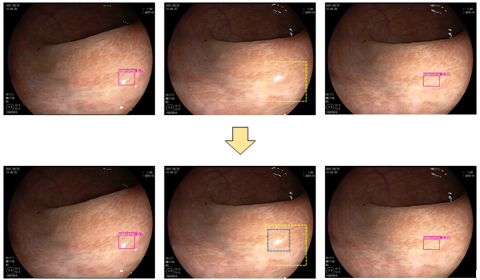

Figure 6 shows an example of how the Seq-Bbox mechanism supplements the anchor for missed intermediate frames during adenoma detection in colonoscopy videos by establishing Tubelet Bbox links. The images are frames extracted from the T1 and T5 group detection videos.

From the top of Figure 6, the detection result without the Tubelet Bbox link from the original network shows a missed detection in the intermediate frame when detecting a polyp in two directions. This leads to an increased miss detection rate, which reduces the recall rate for adenomas. However, with the improved algorithm, the Tubelet Bbox link is established between adjacent frames. This link uses bilinear interpolation to locate the detection box in the intermediate frame. After generating the detection box, the motion information of the adenoma is matched, and the bounding box is shrunk to increase the IOU with the Ground Truth, improving the accuracy of detection. The final detection box confidence is averaged from the detection boxes of the previous and next frames.

Figure 6. Anchor supplementation via Seq-Bbox mechanism